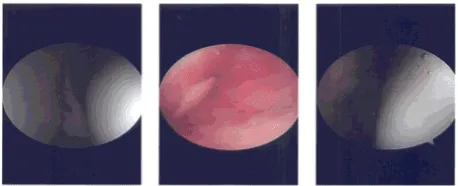

Preop antibiotic was given. Tourniquet was inflated. Time-out was called. Lateral anterior portal was made for the arthroscope and the examination of the knee was done. It showed osteoarthritic lesions on the posterior surface of the patella.

Examination of the medial compartment showed medial meniscus tear. The Medical entry portal was made using a spinal needle. Medial meniscectomy was performed using a shaver and biters.

Examination of the intercondylar notch showed intact ACL. Examination of the lateral tibiofemoral compartment showed a tear of the lateral meniscus, which was cleaned using biters as well as shaver.

Examination of the patellofemoral compartment showed osteoarthritic changes of grade 3 to grade 4. Decision for microfracture was done and was done to microfracture the posterior surface of the patella.

The scope was entered from the medial entry portal and findings reconfirmed and final balancing of the meniscectomy was performed. The knee was drained completely and irrigated and final pictures were saved.

Intraoperative photo